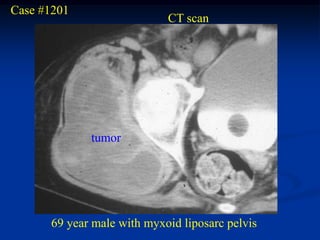

Case #1201 CT scan tumor 69 year male with myxoid liposarc pelvis

• 228.

• 229.

• 230.